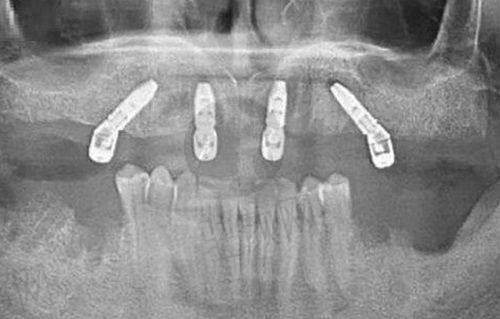

门诊部配备了高端的口腔诊疗设备,引入了智能数字化技术,以确保诊疗的精细性和效率。在种植牙方面,采用数字化微创种植技术,如闺蜜的妈妈做的半口 All - on - 4 种植,医生先用德国 CBCT 拍 3D 口腔片,精细定位神经和血管,再用导板辅助种牙,伤口小,术后当天就能戴临时牙吃饭,3 个月即可修复好。在牙齿矫正方面,拥有“美亚仪 AI 导航口扫仪”,用小探头在嘴里扫一圈,3 分钟就能在电脑上看到矫正后的 3D 成效,还能模拟每个阶段的变化,告别了传统咬石膏模型的方式。

众多患者对深圳麦芽口腔门诊部(福田机构)给出了良好的评价。张先生(56 岁,半口种植)表示,在国有医院问半口种植要 18 万还不包括骨粉,而在麦芽找郑苍尚院长做的韩国登腾半口种植,活动价 10 万(含骨粉 + 基台 + 冠),前期的 CBCT 检查和牙周治疗走了医疗保险,报销了 1200 元,实际花了 9.88 万,现在吃饭香,说话不漏风,比预期省太多了。李女士(32 岁,补牙 + 洗牙)称,蛀牙拖成大洞,去麦芽补牙(美国树脂 298 元) + 洗牙(128 元),补牙走医疗保险报销了 142 元,洗牙自费,原本总共花 284 元,因当天医疗保险日满 300 元减 50 元,末尾实付 234 元,医生还耐心教她用牙线,体验感良好。明明妈妈(宝妈,7 岁儿童补牙)说,明明蛀牙 3 颗,在别家医院吓得哭到做不了,来麦芽后,医生拿动画片吸引他,边看边补牙,用的儿童玻璃离子材料 180 元/颗,医疗保险报了 91 元,3 颗自付 267 元,还送了卡通牙具套装,现在娃每天主动刷牙。